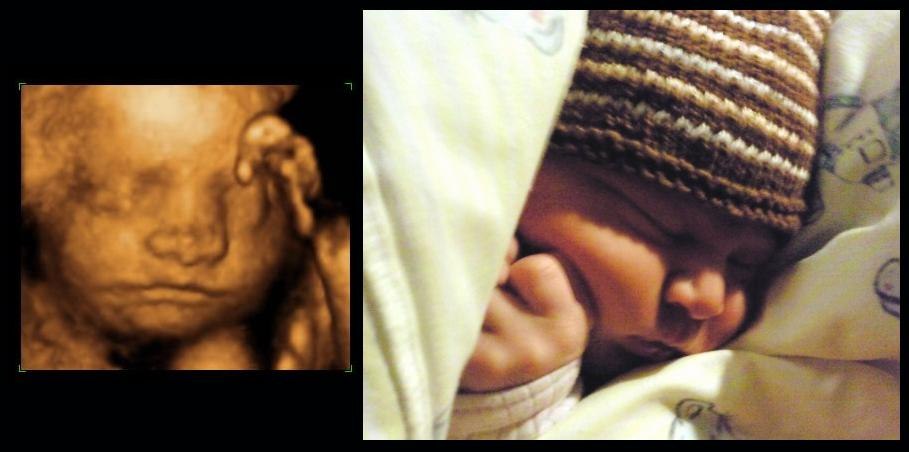

Syntes det er vildt! elsker 3d..Håber jeg kommer til at opleve det igen en dag..Peter sys det ser råklamt ud så tager bare en veninde med

Syntes oplevelsen er helt fantastisk og når man har muligheden for at lure den kage der er i ovnen..så kan jeg sgi ikk la være